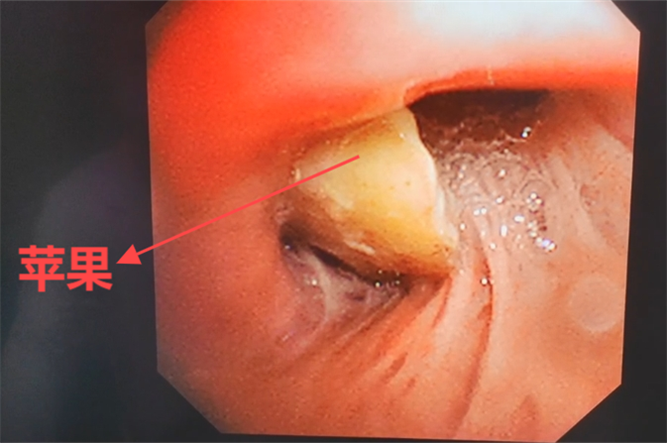

在右肺上葉前段,一塊“三角形”異物乍現(xiàn),剛開始還以為是個痰塊,仔細(xì)辨別后發(fā)現(xiàn)為蘋果塊,取出后發(fā)現(xiàn)蘋果塊有1.2cm這么大。